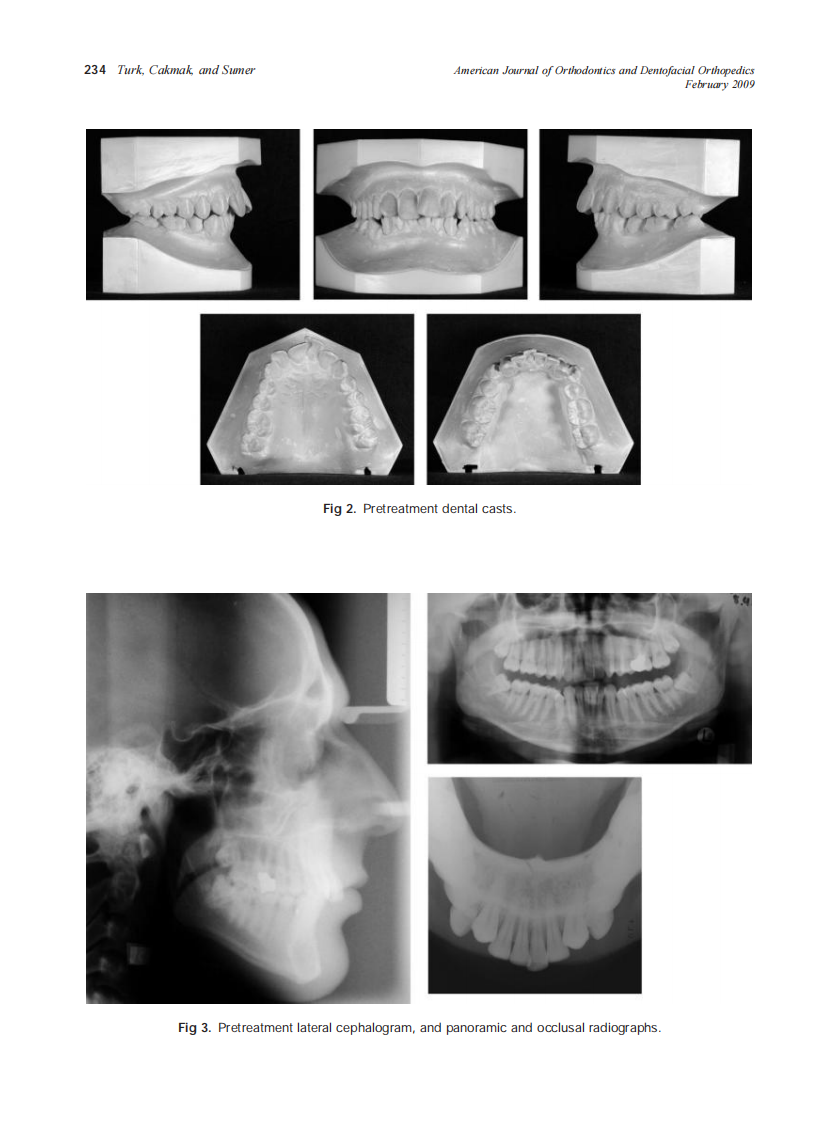

AJO-DO

2009_135_2_232_240_Turk.pdf